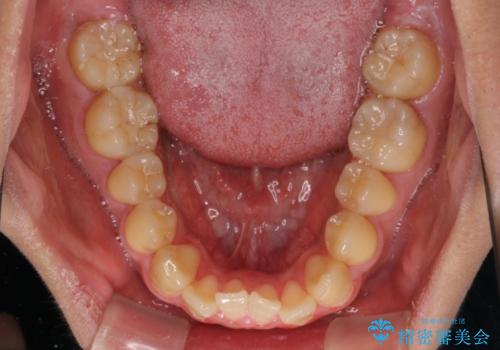

- 前歯のデコボコとクロスバイトを気にして来院された患者様です。

クロスバイトはありましたが、叢生の程度としては酷くなかったため、ワイヤー矯正でもマウスピース矯正でも、好きな方を選択していただきました。

気になっていたクロスバイトは速やかに改善され、1年間で治療を終えることができました。

治療開始前は汚れが多く、全体的に歯肉が腫れていましたが、矯正治療を通して腫れも少しずつ改善されました。